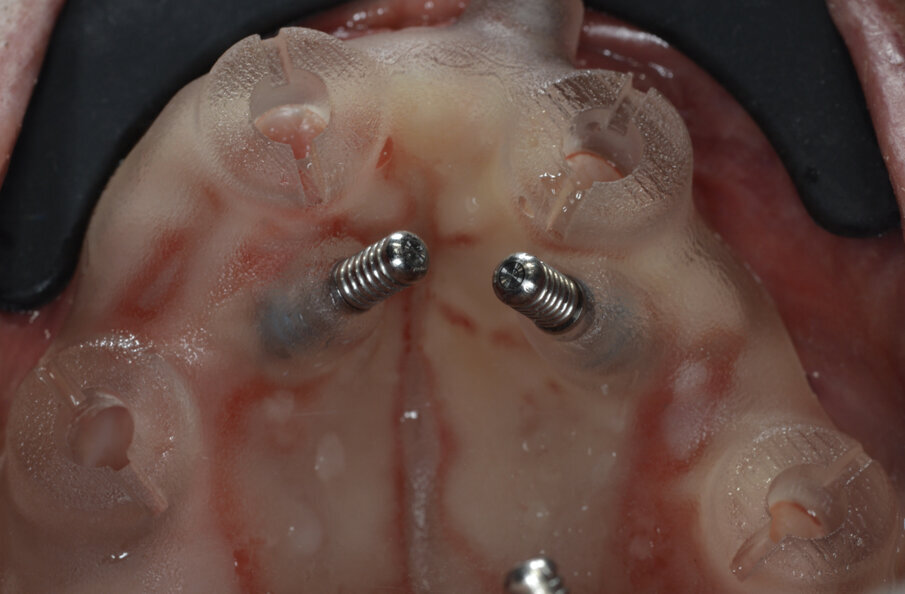

Mostriamo di seguito l’esecuzione di un lavoro di protesi ibrida su impianti tipo Toronto su sistematica OT Bridge (Rhein83, Italia). Il paziente, edentulo con più di 80 anni di età viene operato in chirurgia guidata (Figg. 11, 12). Vengono inseriti 4 impianti TSIII (Osstem, Korea) del diametro di 4 x 8.5 in zona 16, 3.5 x 11.5 in zona 12, 3.5 x 11.5 in zona 23 e 4 x 8.5 in zona 27. La progettazione è avvenuta con il software RealGuide (3Diemme, Italia) sfruttando le informazioni del montaggio dei denti della protesi totale. Nonostante la progettazione accurata, gli impianti non si sono potuti collocare in perfetto parallelismo per le condizioni ossee scarse. Quindi tra le varie fixture sono presenti disparallelismi, proprio per questo abbiamo deciso di utilizzare la sistematica OT Bridge (Rhein83, Italia) che risulta particolarmente vincente in caso di parallelismo tra i monconi. Abbiamo inserito gli abutment OT Equator (Rhein83, Italia) già al tempo della chirurgia e li abbiamo ricoperti con le viti di guarigione scegliendo la chirurgia one-stage (Figg. 13, 14).

Fig. 11_Visione occlusale di un mascellare edentulo.

Fig. 12_Template chirurgico realizzato da New Ancorvis fissato con pin.

Fig. 13_OT Equator inseriti al tempo della chirurgia.

Fig. 14_Healing abutment per chirurgia one-stage.